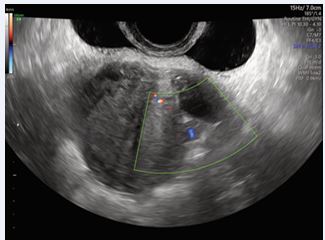

A 29-year-old female presented to our Obstetric Emergency Unit with the main complaint of irregular spotting and vaginal bleeding lasting 7 days. Her medical and surgical history was unremarkable. In her obstetric history, she had undergone a cesarean section at 37 weeks due to fetal distress during induction for an IUGR fetus with trisomy 21. Upon examination, there were no general concerns. At speculum assessment, the cervix appeared normal, with no discharge, and minimal residual uterine bleeding was noted in the vagina. On bimanual examination, the cervix was upward-pointing, the uterus was bulky and anteverted, and the bilateral fornixes were free and non tender. Laboratory tests revealed normal results, with hemoglobin levels within the reference range. A positive β-hCG test indicated a level of 7118 IU/L, which rose to 14,452 IU/L after 48 hours, showing less than a doubling effect. Transvaginal ultrasound performed in the emergency unit showed an empty uterine cavity with clearly defined endometrium. A small, irregular gestational sac-like structure corresponding to five weeks was identified in the lower uterine segment anteriorly, with a vitelline sac and a small embryo without cardiac activity. Both adnexa were normal, and no free fluid was observed in the Douglas pouch. Doppler imaging confirmed the diagnosis of a cesarean scar ectopic pregnancy, revealing excessive vascularity in the hyperechoic rim of the choriodecidual reaction. Ultrasound findings were later corroborated by expert sonographers, with no signs of uterine dehiscence or rupture. Initial management involved monitoring clinical signs and serial β-hCG levels. The patient was asymptomatic, and after thorough counseling regarding pregnancy outcomes (expectant management versus pregnancy interruption), she decided for interruption. Intramuscular Methotrexate was then administered (50 mg/ im). By Day 3, a significant increase in β-hCG levels (22,797 IU/L) and enlargement of the gestational sac (19x17 mm) prompted the decision to administer a single oral dose of 600 mg Mifepristone. Unfortunately, this approach failed to terminate the pregnancy (Figures 1-3). By Day 5, ultrasound imaging confirmed the presence of an embryo with cardiac activity. After additional counseling, the patient consented to a further intervention.

Figure 1: Transvaginal ultrasound - Anteverted and anteflexed uterus, normal in size and regular in morphology with heterogeneous myometrial echotexture consistent with diffuse uterine fibromatosis.